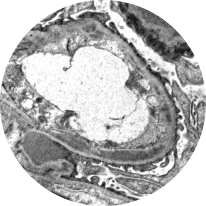

Light microscopy

Provides initial diagnostic evaluation, assessing patterns of glomerular injury. Does not distinguish between forms of glomerulonephritis2,21

Healthy glomeruli

MPGN pattern of injury

(C3G/IC-MPGN)